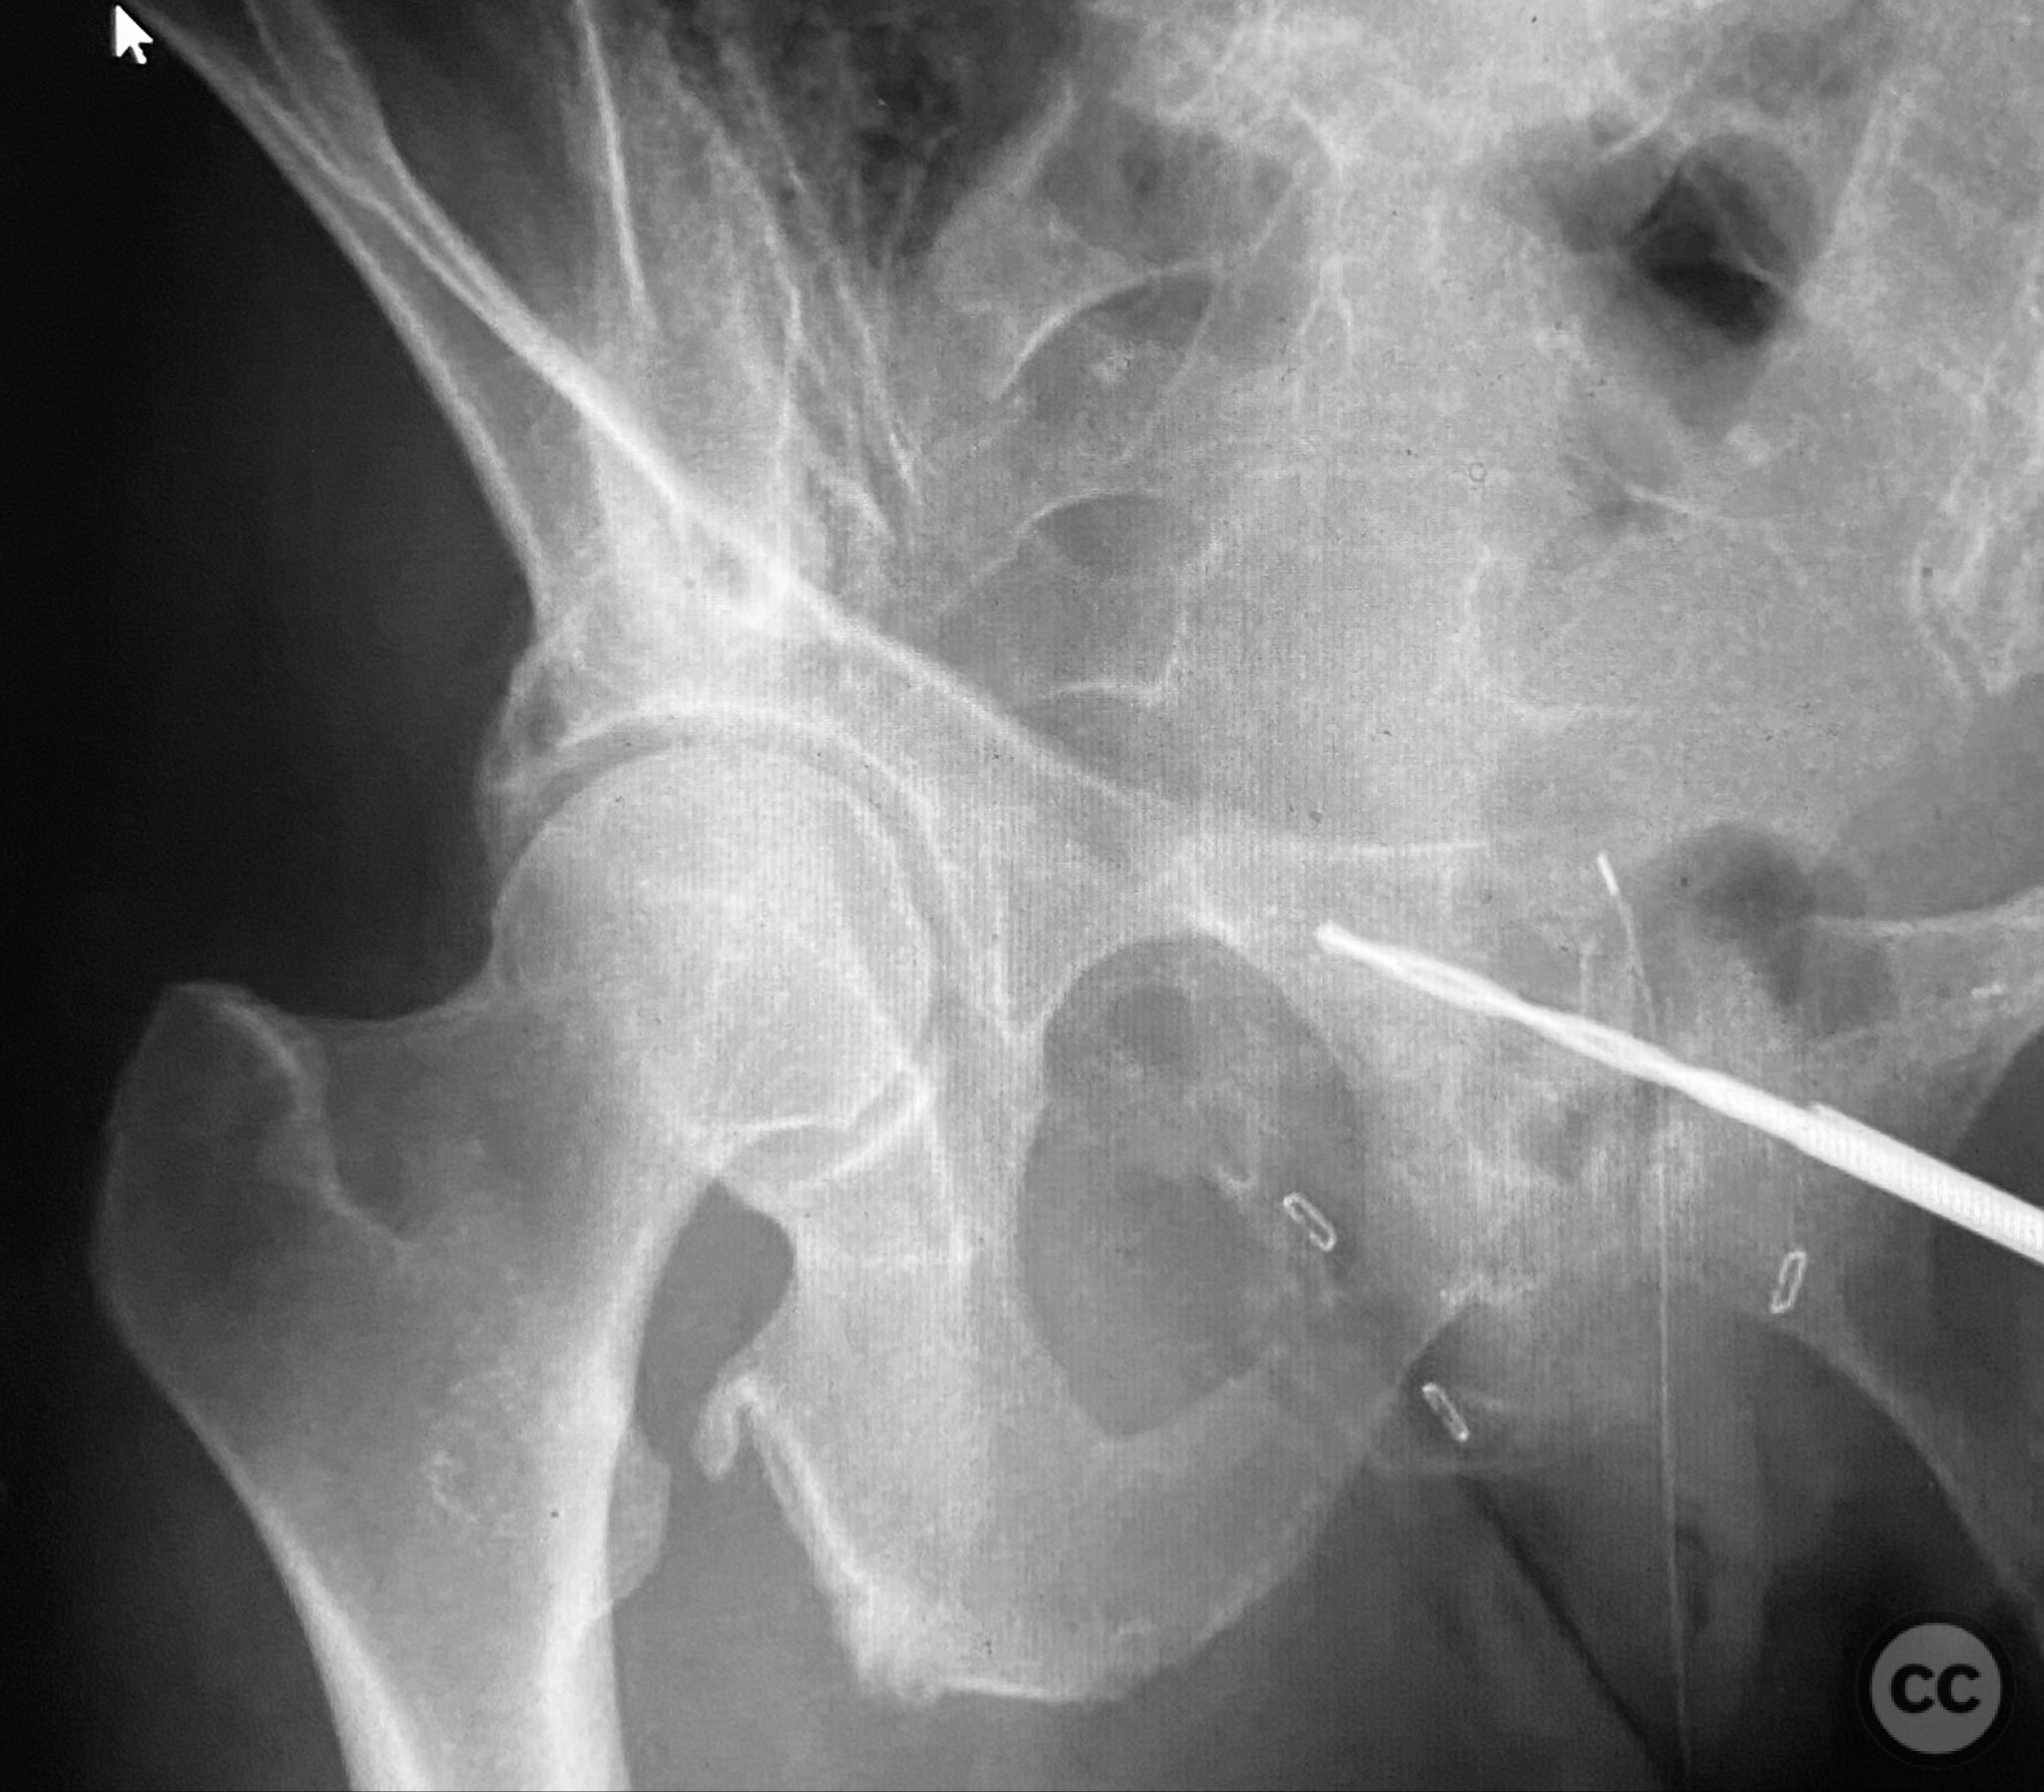

Intraoperatively, a 3.5mm drill was used through a protective sleeve to initiate the screw pathway across the superior pubic ramus. Due to poor bone quality, a 2.5mm drill was subsequently employed; however, resistance was encountered as the drill tip engaged the dense cortical apex of the anterior acetabular wall. The drill became lodged in this region. To avoid drill breakage, manual extraction using pliers was considered; however, the surgeon elected to carefully deflect and advance the drill manually, successfully completing the pathway. Screw length was measured directly from the embedded drill tip. A 4.5mm cortical screw was then inserted trans-symphyseally along the prepared medullary canal, achieving stabilization of the unstable ramus fracture. Postoperative CT confirmed appropriate screw trajectory and demonstrated the dense cortical bone at the anterior acetabular wall where the drill tip had engaged.